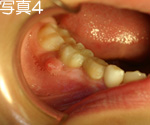

写真3、4を見て下さい。虫歯のある乳歯の根に赤い膨らみがありますよね。これが歯の根が腫れている状態です。根っこに膿を作って、バイ菌が繁殖しますが、ここは永久歯が出来ている真横です。この場所で炎症が続くと、永久歯がやられます。永久歯表面の石灰化が障害されるのです。